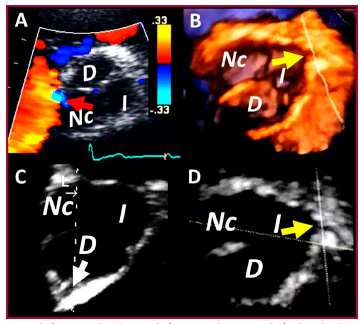

Evaluación con ecocardiografía 2D y 3D de una arteria coronaria con trayecto retroaórtico